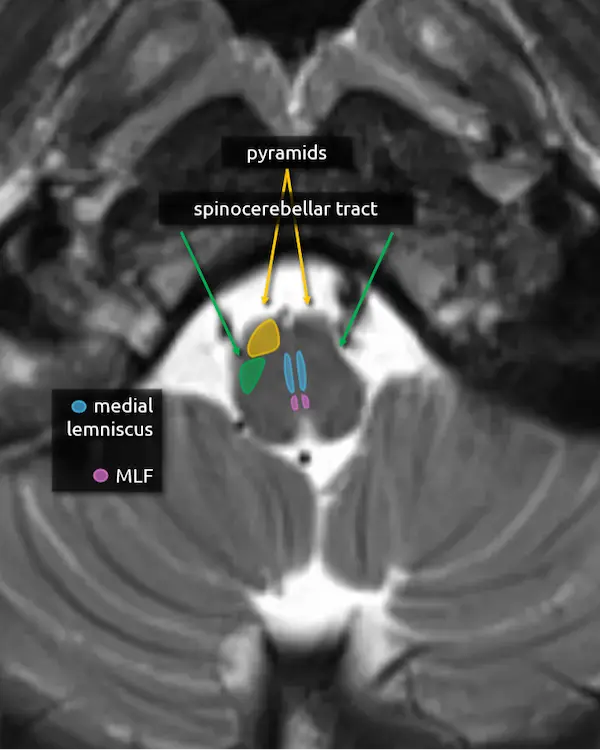

1. Pyramids:

The medullary pyramids contain the corticospinal tract and corticobulbar tract, which are sometimes collectively called the pyramidal tracts. They are named due to the shape they form on the ventral surface of the medulla, which usually becomes more pyramid-like inferiorly.

2. Spinocerebellar tracts:

The spinocerebellar tracts are ascending tracts from the spinal cord to the cerebellum involved in proprioception of the trunk and lower limbs. They are separated into ventral and dorsal divisions; the dorsal division travels to the cerebellum via the inferior cerebellar peduncle and the anterior division goes through the superior cerebellar peduncle. To reach the superior cerebellar peduncle, the anterior spinocerebellar tract travels along the lateral margin of the corticospinal tract through the pons. The spinocerebellar tract is best approximated posterior to the pyramids in the mid to lower medulla, where the ventral and dorsal division remain together.

The upper limb equivalent of the spinocerebellar tract is the cuneocerebellar tract, which is smaller and located medially.

Lesions involving these tracts will cause ataxia.

1. Pyramids

2. Spinocerebellar tracts

3. Medial lemniscus

4. Medial longitudinal fasciculus (MLF)